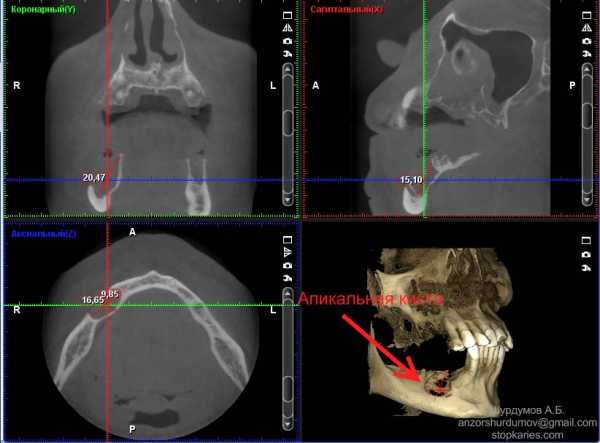

- Радикулярная киста, апикальная киста, кистогранулема, гранулема – дальнейшее развитие периодонтита, при отсутствии своевременного лечения. Представляет собой образование округлой формы выстланное эпителием. Само по себе практически никогда не болит и медленно растет, может в итоге привести к перелому челюсти в результате истончения кости, обнаруживается при обострении или на рентгеновских снимках во время лечения зубов. При обострении могут давать постоянные ноющие боли без четкой локализации, обычно указывают только пораженную сторону челюсти, либо предъявляют жалобы на причинный зуб.

Радикулярная/апикальная кита на компьютерной томограмме.